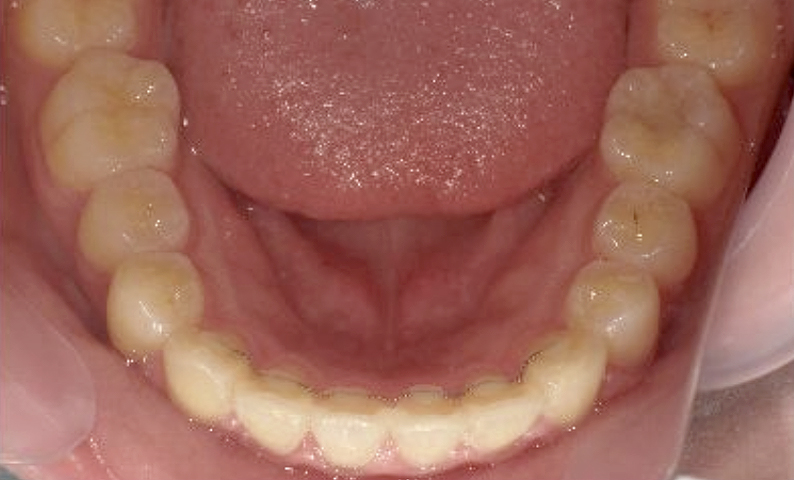

症例_005 上下顎の部分矯正

治療期間:11ヶ月金額:54万円+税女性前歯のガタガタ捻転歯

| Before | After |

|---|---|

|